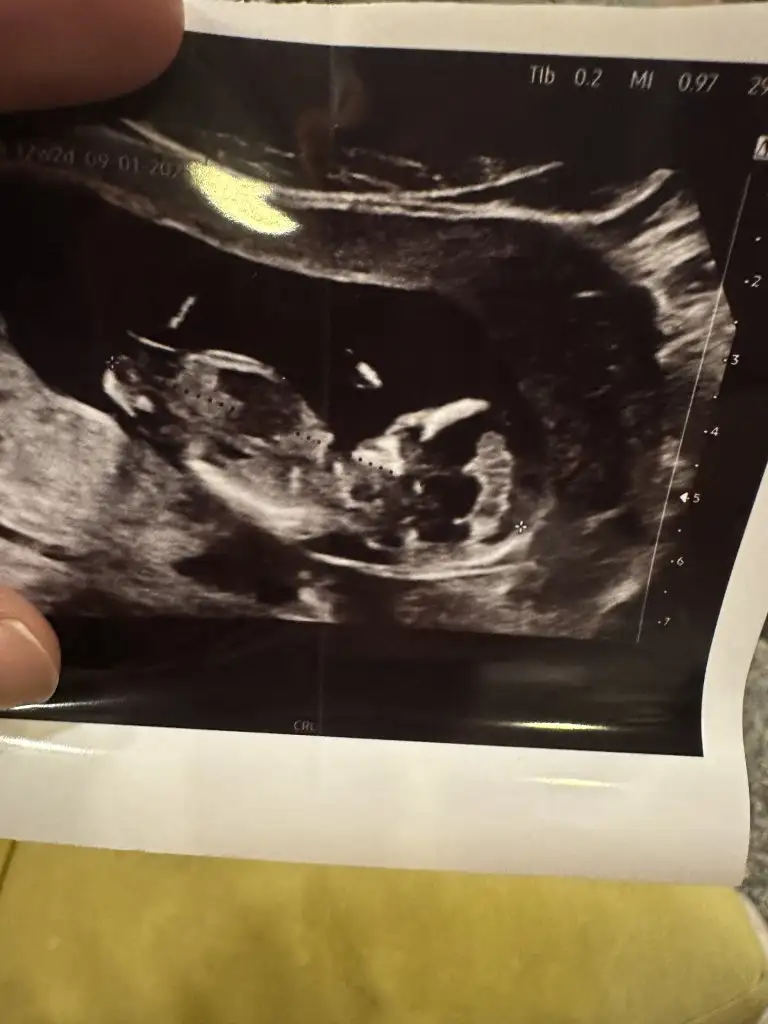

Evett güncelleme yapıyorum son ultrason fotoğrafımız 🤍 düşüncesi olan var mı 🥰

• IMG_5851.webp

IMG_5851.webp

42,2 KB · Görüntüleme: 103